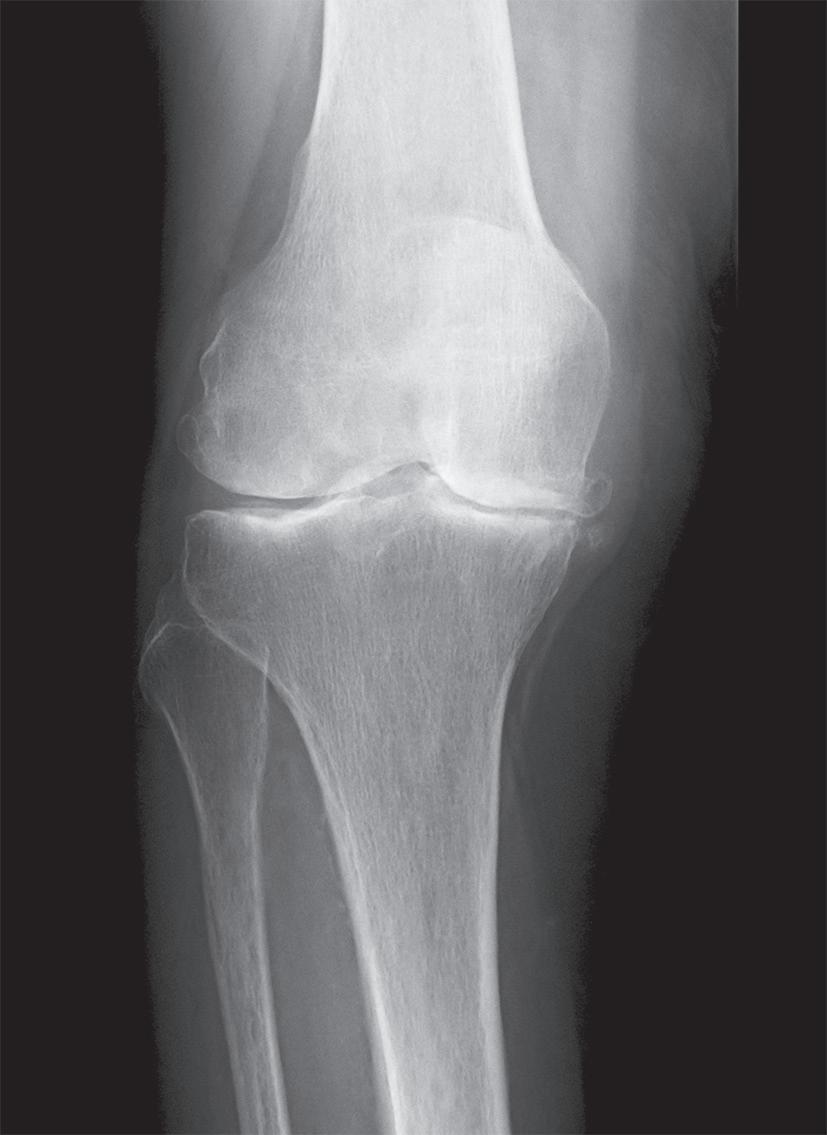

kloubu nebo jako startovací bolest na začátku pohybu. Později se přidává i bolest klidová a noční. Původní krátká ranní ztuhlost přechází ve zhoršování funkce a dochází k postupnému omezení rozsahu hybnosti v kloubu. Objektivně nacházíme defiguraci kloubu na podkladě tvorby artrotických osteofytů. Objevuje se typická deformita ve smyslu varozity nebo valgozity (genu varum, genu valgum, obr. 19.2, obr. 19.3), v těžších případech doprovázená různým stupněm flekční kontraktury (genu flectum). Typicky jsou přítomné drásoty (krepitus) při pohybu kloubu, palpační bolestivost, v období dekompenzace i známky reaktivní synovialitidy či výpotku. Dochází k laxitě –insuficienci vazivového aparátu na konvexitě deformity, a naopak jeho retrakci na konkavitě. Zjišťujeme omezení rozsahu pohybu různého stupně, v pozdním stadiu může přejít až v semiankylózu, nebo dokonce ankylózu, prakticky vždy ve funkčně nevýhodném postavení.

Základem diagnózy je klinické vyšetření doplněné o rentgenový snímek obvykle ve dvou projekcích

Obr. 19.3: Valgózní deformita kolenního kloubu (a) a rentgenový  nález úhlové deformity s nálezem pokročilých artrotických  změn (b)

(předozadní a bočná). Na rentgenovém snímku se gonartróza zpočátku projevuje přihrocením interkondylické eminence a subchondrální sklerózou v místě přetížení, později zúžením, případně až zánikem kloubní štěrbiny, vznikem osteofytů, pseudocyst a případnou úhlovou deformitou. Dle nálezu rovněž klasifikujeme stupeň gonartrózy podle Kellgrena-Lawrence (viz kap. 17, obr. 19.4), což má praktický význam v indikaci farmakoterapie i balneoterapie.